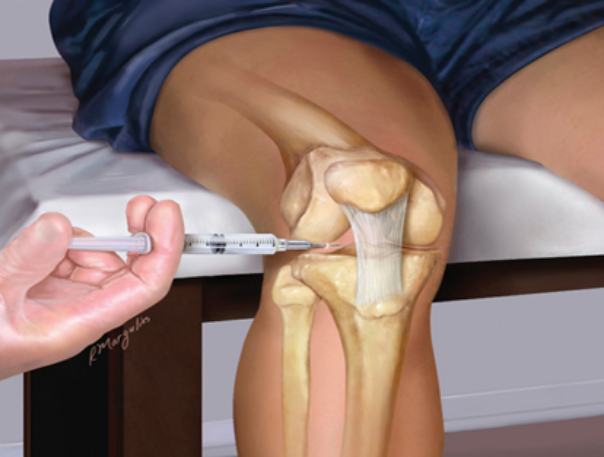

Infiltraciones

En ocasiones es de utilidad administrar medicación en el interior de la articulación o en las estructuras que la rodean. Con estas terapias conseguimos disminuir el dolor y la inflamación articular para ayudar al control o una mejor recuperación de las lesiones.